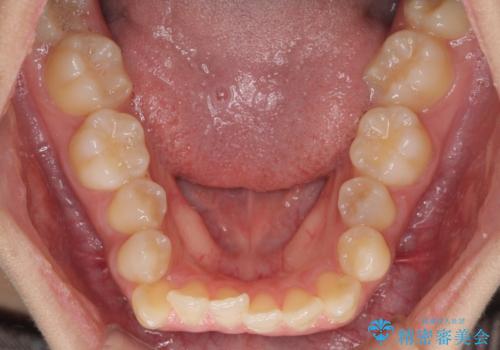

- 上下のデコボコと奥歯の咬みにくさを気にして来院された患者様です。

上顎骨の幅が下顎骨よりも小さく受け口傾向であったため、拡大装置により上顎骨の骨幅を広げて上下関係を改善し、その後インビザラインにて歯並びを整えることとしました。

下顎歯列は上顎歯列内に収まるように並んでいますが、上顎骨の幅が狭いと、下顎臼歯が全体的に舌側に傾斜した歯列となってしまいます。

舌側に傾斜した歯列は奥歯に力の負担がかかりやすく、歯磨きがしにくいなどの問題があるため、上顎骨拡大により舌側傾斜を改善することが可能となります。